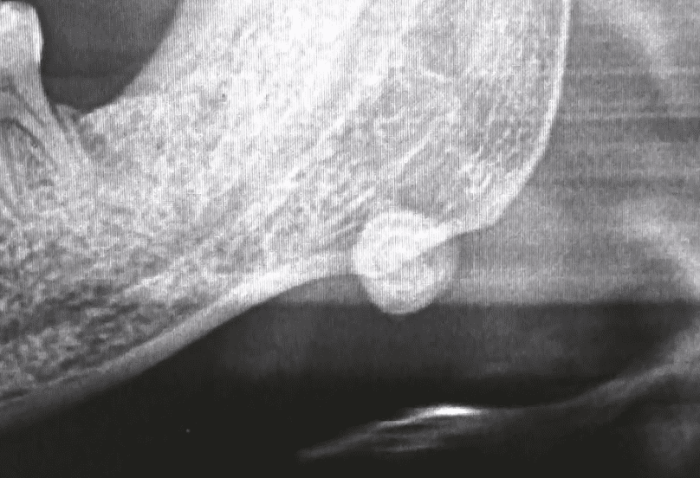

2. 影像學診斷

除了直接的身體檢查外,影像學檢查提供了更準確的輔助診斷方式,特別是在判斷唾液腺結石的大小、位置和影響範圍方面。

超音波檢查(Ultrasound, US): 超音波因其操作方便、無輻射且適合用於唾液腺,是第一線的成像選擇。超音波可以清晰顯影位於腮腺或頜下腺的結石,並幫助醫生確認結石的大小及其是否阻塞導管。此外,這種診斷方式對於動態唾液流的評估也非常實用,能夠進一步區分功能異常和實質阻塞的原因。

電腦斷層(Computed Tomography, CT): 若超音波不足以清晰診斷或臨床懷疑結石較深藏在腺體組織中,醫生可能採用 CT 篩檢。與其他成像技術相比,CT 可提供更多結構性的三維資訊,並在結石成分具有較高密度特性的時候有較佳的辨識效果,因此是對高密度的磷酸鹽和碳氫磷石灰結石的理想選擇。